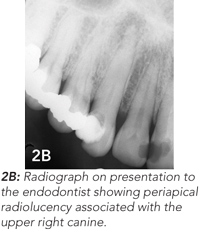

A healthy 41-year-old woman presented to her GP with a non-healing pimple on her right nasolabial fold (Figure 2A). The GP referred the patient to a surgeon who attempted to excise the lesion. Reportedly, the lesion resolved, only to recur 3 months later. By this time, the surgeon suspected a dental aetiology, and referred the patient to an endodontist. Radiographic examination suggested that the lesion was related to an infected upper canine. A radiolucent area around the root of the tooth was characteristic of a periapical abscess (Figure 2B). The tooth was treated endodontically (Figure 2C), and the skin tract resolved.